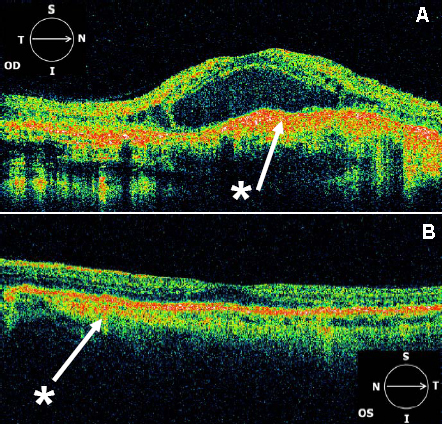

Figure 6. OCT3 scans (6 mm) centered on the fovea. From the right eye (A) and left eye (B) of affected individual III:4. Hyperreflectivity (*) at the level of the RPE-choroid complex is noted throughout the macula

in the right eye (OD) and to a lesser extent in the left eye (OS). The right eye also demonstrates intraretinal cysts throughout

the macula and a large central retinal detachment. The left eye demonstrates flattening of the foveal pit and loss of the

outer nuclear layer temporal to the fovea.